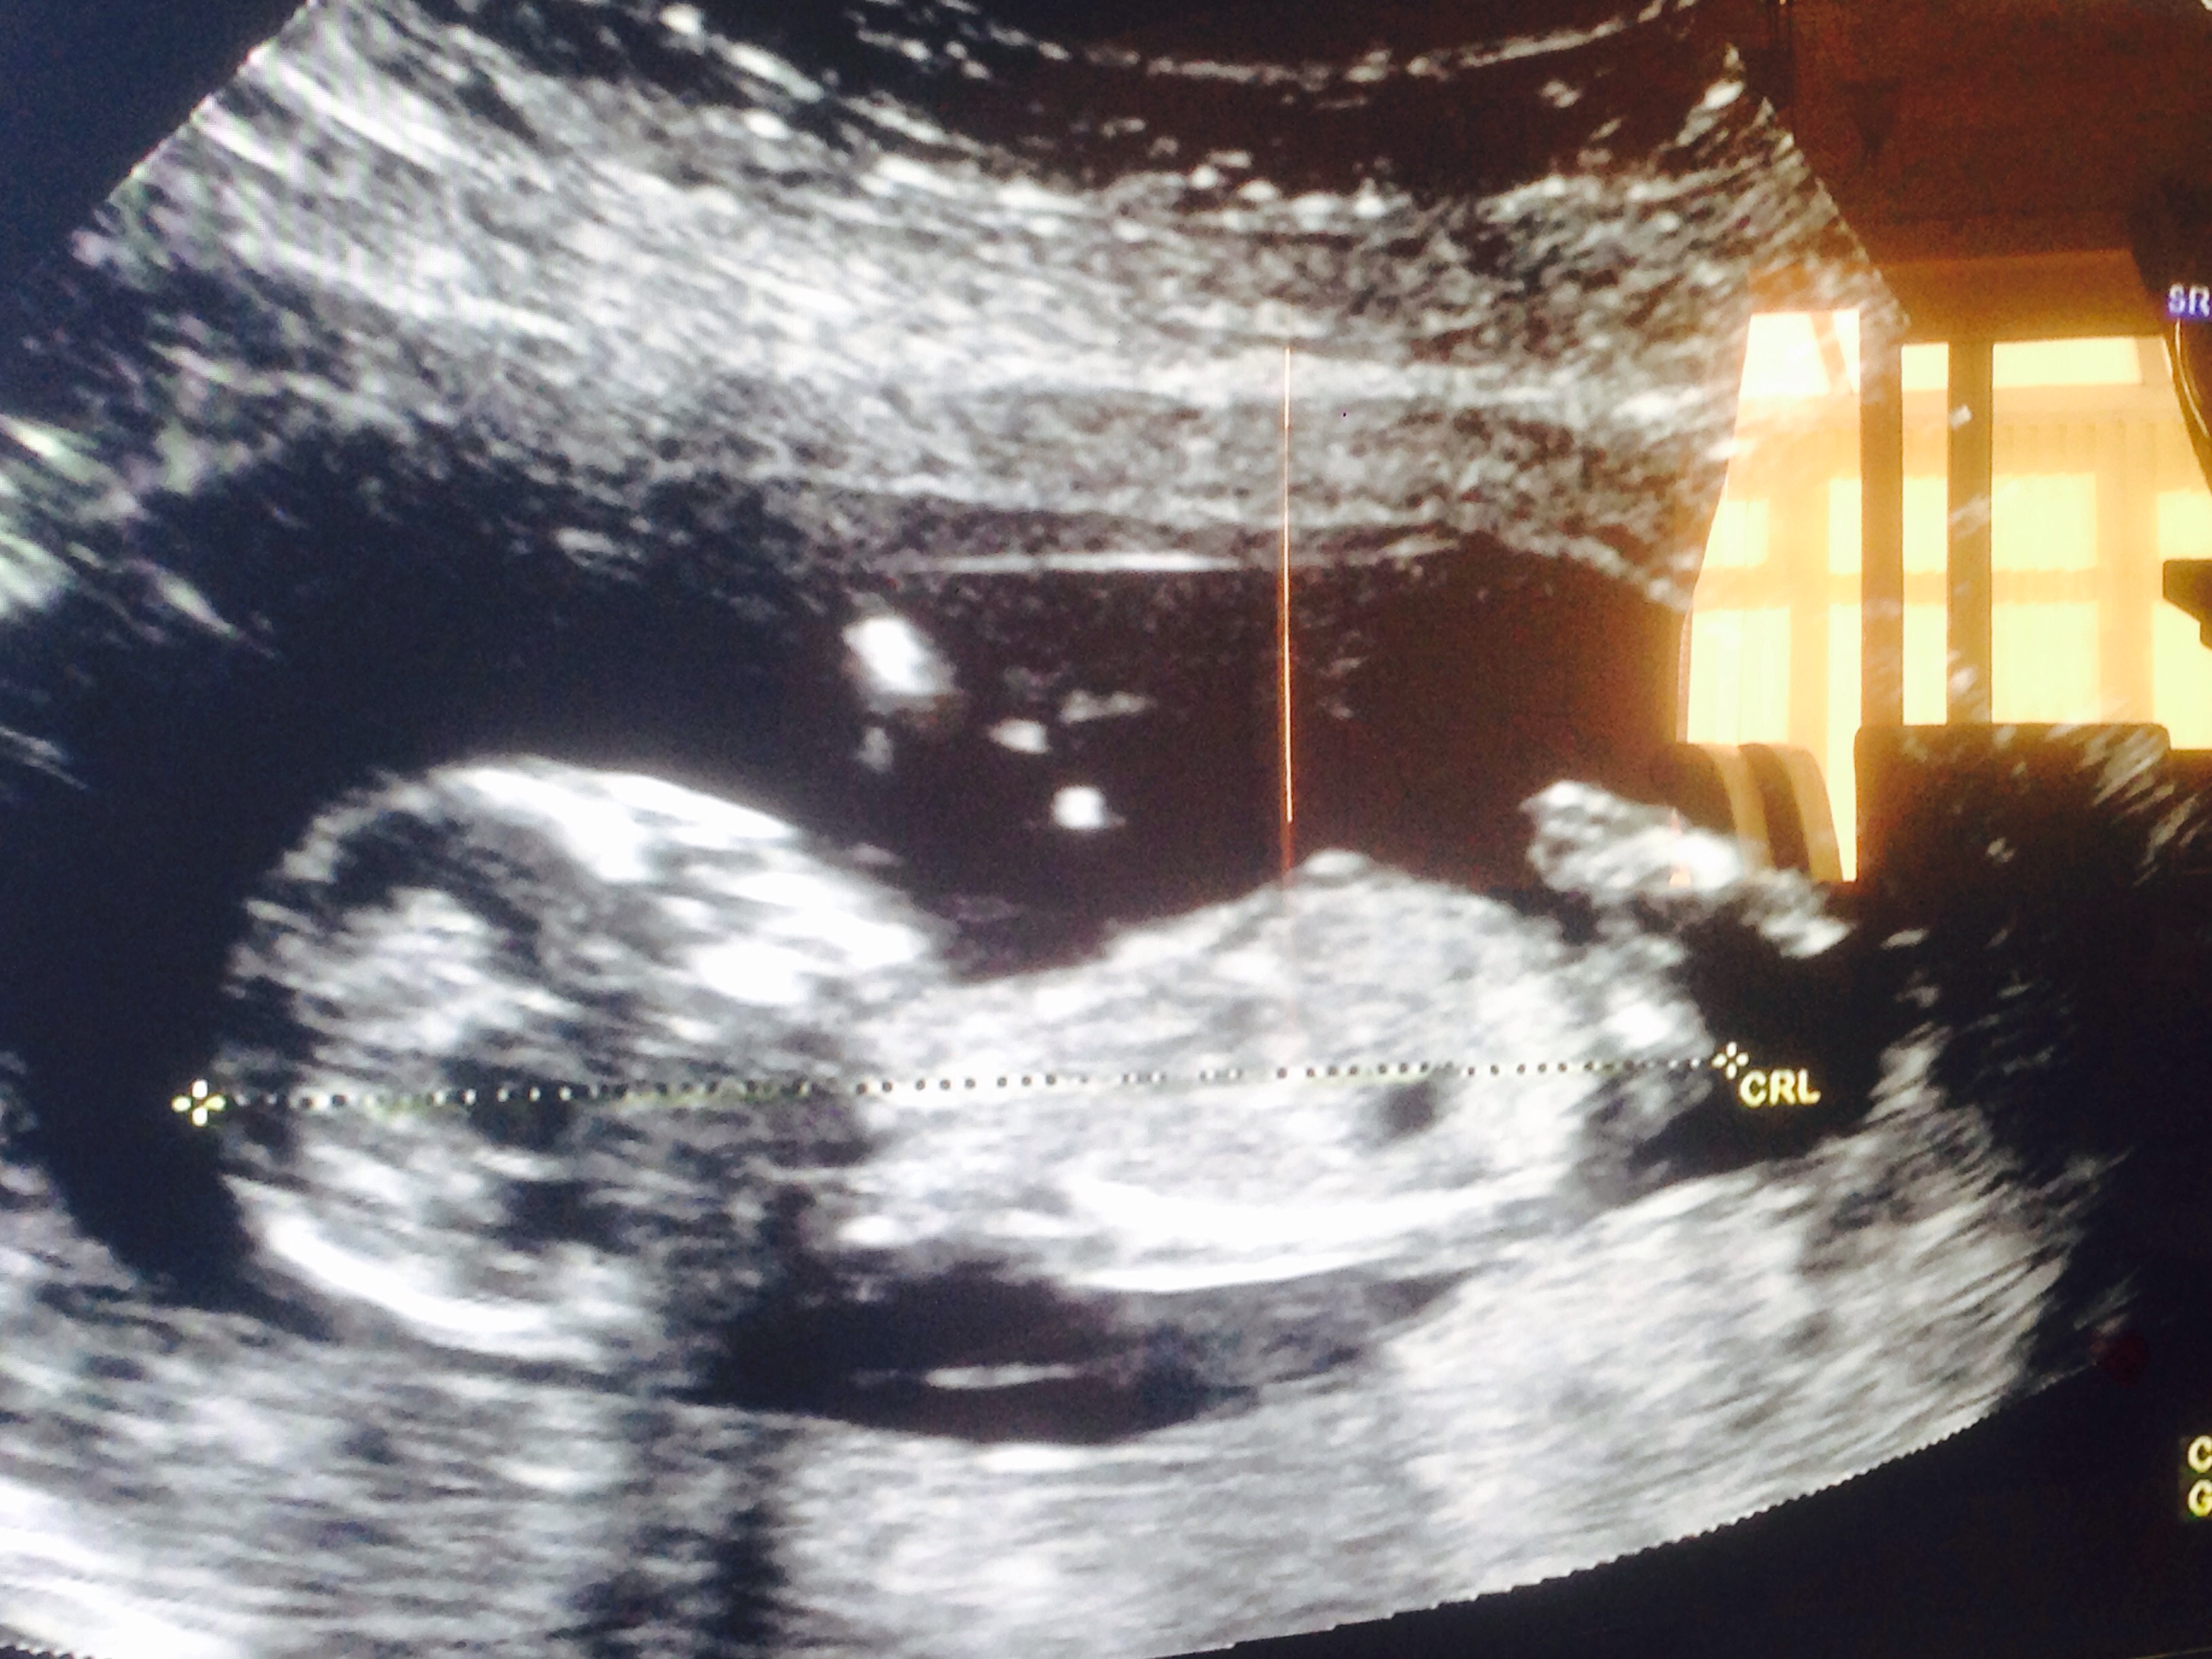

Scan dated me as 13 weeks. I already have a little boy. Any guesses? I'm dying to know! Attachment 27571Attachment 27571Attachment 27572Attachment 27573